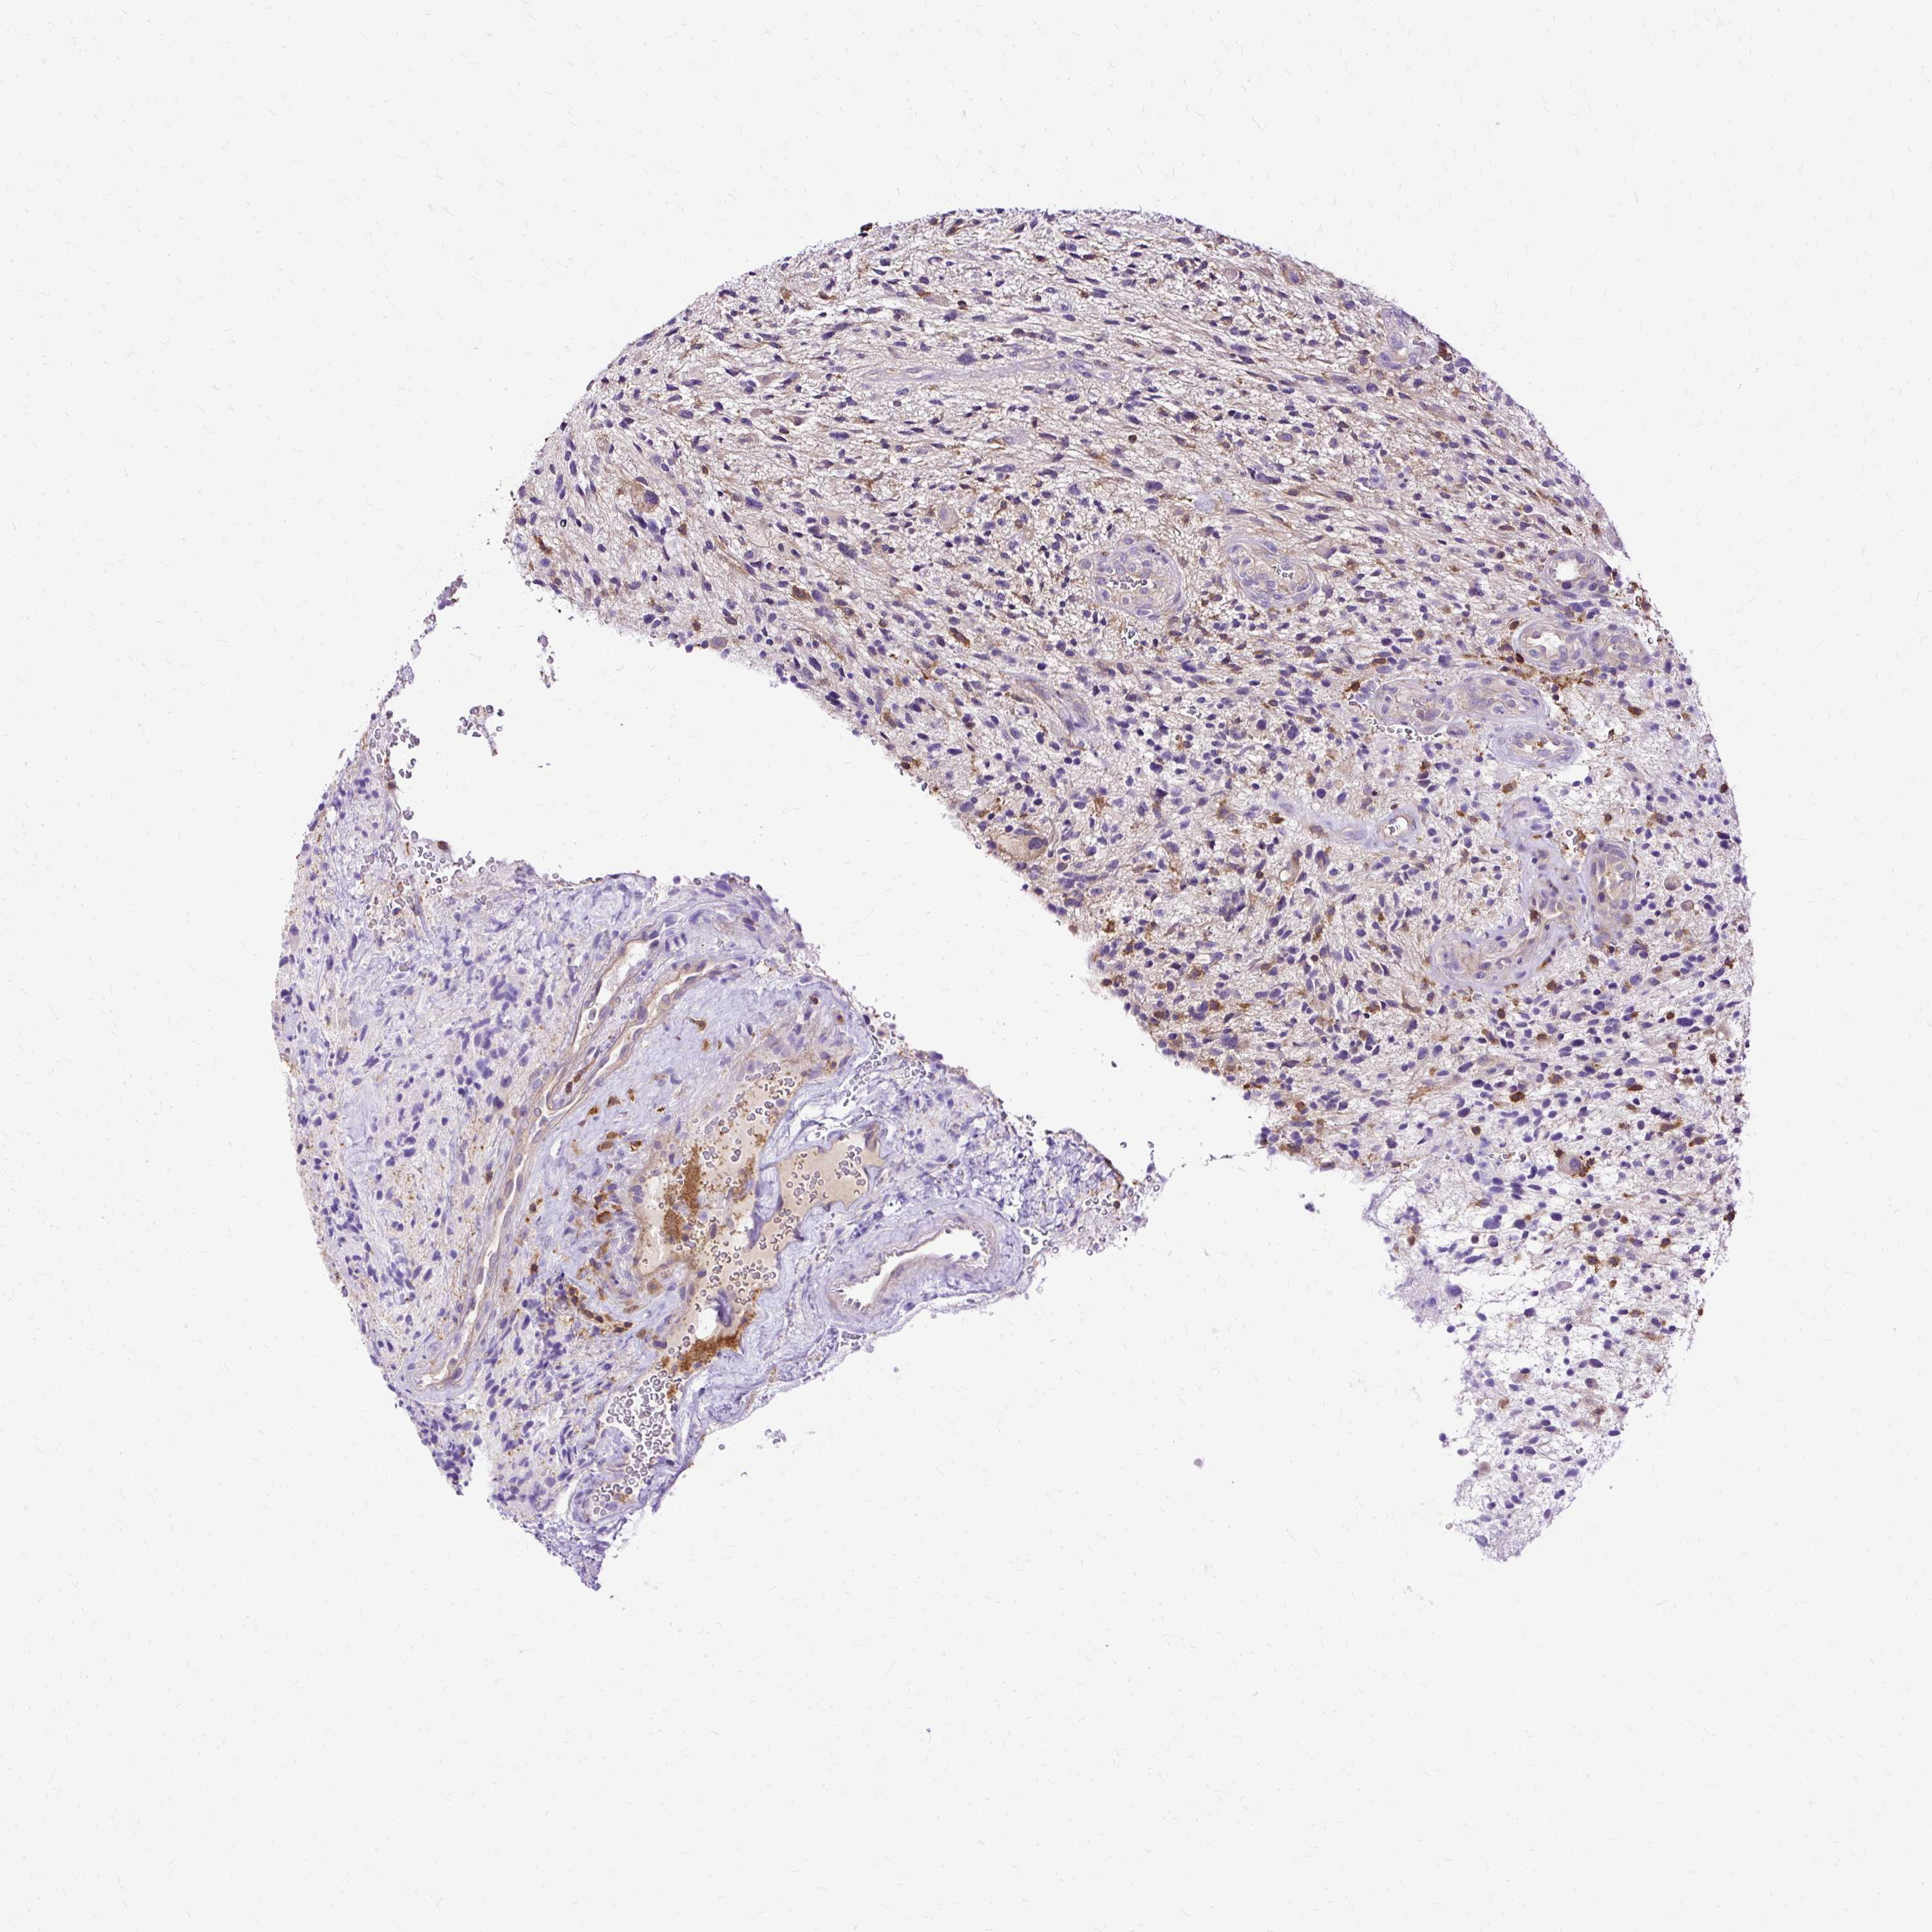

GLIOMA - Protein expressioni

A mouse-over function shows sample information and annotation data. Click on an image to view it in a full screen mode. Samples can be filtered based on level of antibody staining by selecting one or several of the following categories: high, medium, low and not detected. The assay and annotation is described here.

Note that samples used for immunohistochemistry by the Human Protein Atlas do not correspond to samples in the TCGA dataset.

Antibody stainingi

Antibody staining in the annotated cell types in the current human tissue is reported as not detected, low, medium, or high, based on conventional immunohistochemistry profiling in selected tissues. This score is based on the combination of the staining intensity and fraction of stained cells.

Each image is clickable and will lead to virtual microscopy that enables deeper exploration of all samples and also displays staining intensity scores, fraction scores and subcellular localization as well as patient and tissue information for each sample.

Antibody HPA053874

Staining

High

Medium

Low

Not detected

Intensity

Strong

Moderate

Weak

Negative

Quantity

>75%

75%-25%

<25%

None

Location

Nuclear

Cytoplasmic/membranous

Cytoplasmic/membranous,nuclear

Glioma, malignant, Low grade

Glioma, malignant, High grade